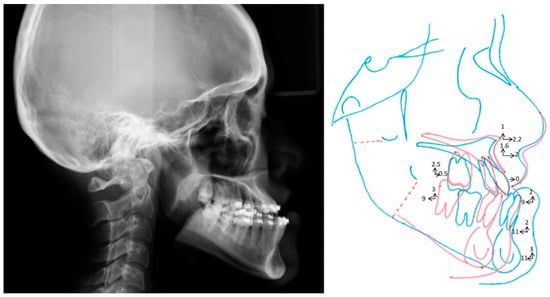

Full descriptions of the 3D computer-aided simulation adopted in this center were previously detailed [29,30,31,32]. After the segmentation of Le Fort I maxillary and bilateral sagittal split osteotomies, the conventional orthodontic 2D plan (Figure 5) was transferred into the virtual scenario; this planning and transferring considered the 2D Taiwanese Chinese cephalometric norms. Through a collaborative teamwork approach between orthodontist and surgeon, further adjustments were performed in midline, roll, pitch, and yaw directions, as well as genioplasty. These patient-specific skeletofacial adjustments were performed before surgical intervention [30], and no bone movement was implemented for the current study. The final 3D image datasets adopted for the transferring of the simulation to actual surgery were adopted as a basis to perform 3D cephalometric measurements using the Burstone analysis method. The 3D cephalometric dataset resulting from this analysis was compared with the 3D norms generated in this study. A 3D digital image dataset was also randomly selected to be adopted in a computer-aided simulation using the Burstone analysis-derived 3D norms.

Figure 5. Practical example of the two-dimensional (2D) planning based on 2D Burstone norms for orthognathic surgery treatment using the single-splint, two-jaw surgery technique. Blue and red colors symbolize the initial bone framework and final maxilla–mandibular repositioning, respectively. Arrows represent the direction and amount of bone segment movements.